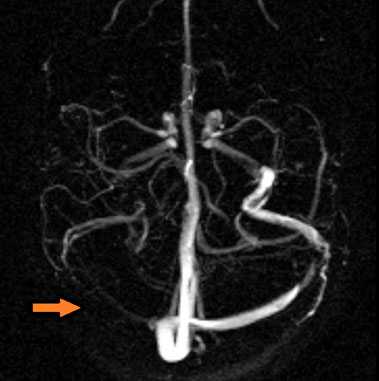

МР-венография - отсутствие визуализации кровотока в правом поперечном синусе и яремной вене.

МР-венография: тромбоз левого поперечного синуса. Отмечается потеря МР-сигнала от левого поперечного синуса.

МР-венография: тромбоз правого поперечного синуса. Отмечается потеря МР-сигнала от правого поперечного синуса.

Тромбоз правого поперечного синуса. Отсутствие феномена «пустоты потока» от правого поперечного синуса на МРТ головного мозга. Отсутствие визуализации правого поперечного синуса на МР-венографии.